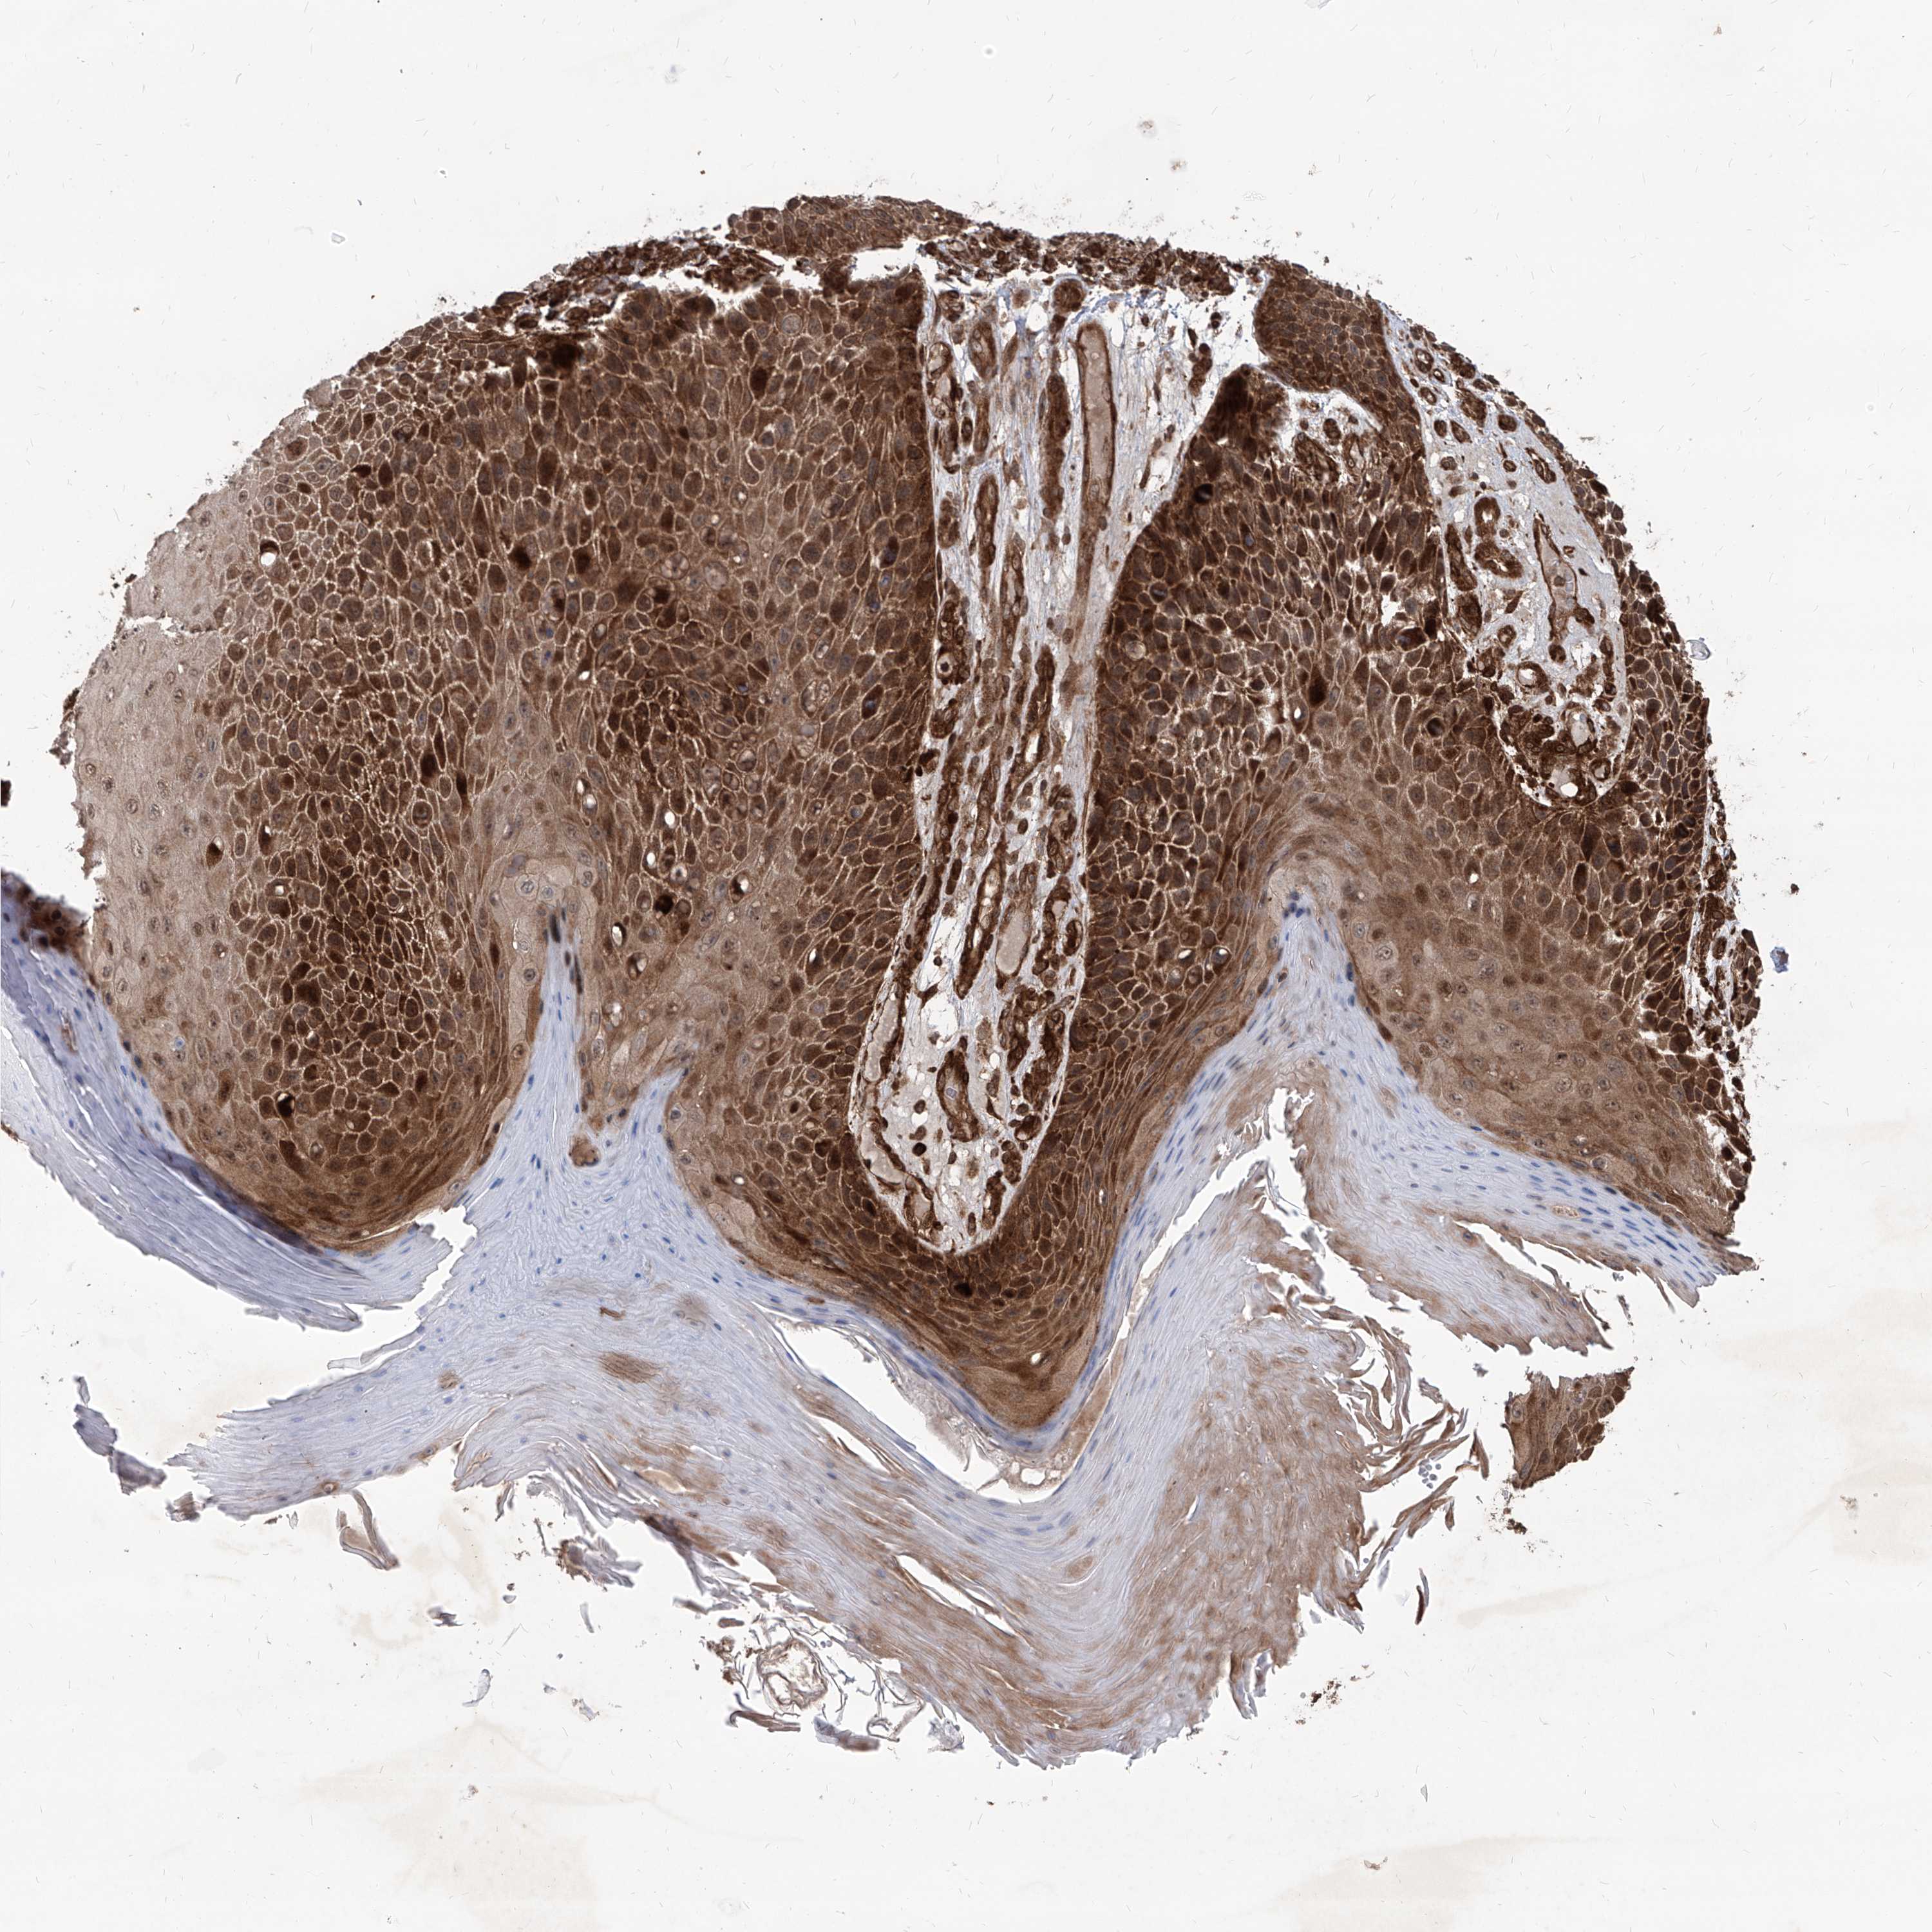

Basal cell and squamous cell cancer

SKIN CANCER - Protein expressioni

A mouse-over function shows sample information and annotation data. Click on an image to view it in a full screen mode. Samples can be filtered based on level of antibody staining by selecting one or several of the following categories: high, medium, low and not detected. The assay and annotation is described here.

Each image is clickable and will lead to virtual microscopy that enables deeper exploration of all samples and also displays staining intensity scores, fraction scores and subcellular localization as well as patient and tissue information for each sample.

Antibody HPA031572

Antibody HPA031573

Basal cell carcinoma

Squamous cell carcinoma, NOS

Squamous cell carcinoma, metastatic, NOS